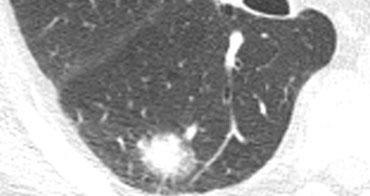

Thành phần đặc và kính mờ

Một kết quả khác từ các nghiên cứu tầm soát là các nốt chứa thành phần kính mờ có nhiều khả năng là ác tính hơn (5).

- Các tổn thương bán đặc có thành phần kính mờ có tỷ lệ ác tính là 63%.

- Các tổn thương không đặc – chỉ có kính mờ có tỷ lệ ác tính là 18%.

- Các tổn thương chỉ đặc có tỷ lệ ác tính chỉ là 7%.

Ở ngoài cùng bên trái là tổn thương chỉ có hình ảnh kính mờ và kế bên là tổn thương có cả thành phần kính mờ và đặc.

Khả năng ác tính là 1:5 đối với tổn thương ở ngoài cùng bên trái và 2:3 đối với tổn thương có cả thành phần kính mờ và đặc.